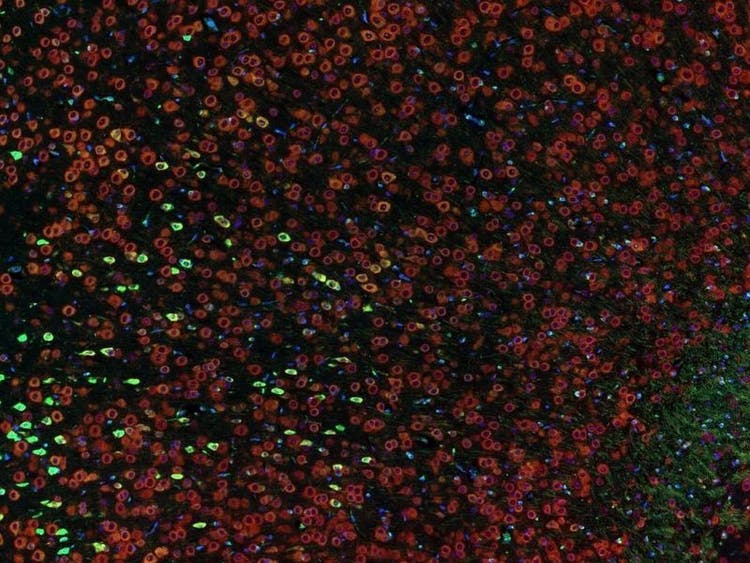

Fluorescence imaging of a mouse brain

While each of these images looks distinct up close, they all come together to form one view of a mouse brain captured with fluorescence imaging.